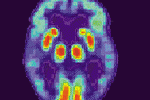

La depressione è una patologia in continuo aumento, è previsto un aumento vertiginoso nei prossimi anni. Secondo le stime dell' Oms nel 2020 sarà la seconda malattia più diffusa al mondo. A lanciare l'allarme alcuni esperti che hanno partecipato... ...